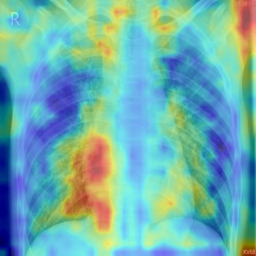

a) Chest X-Ray (Pneumonia) Dataset. We compare a baseline PatchCore system (memory from the full training set, no IL) against our proposed IL strategy using the Chest X-Ray dataset, which begins with 30% seed normal samples. Evaluation is performed on a held-out test set with mixed labels. As shown in Table 1, IL substantially improves performance across multiple metrics. ROC-AUC increases from 0.6834 (baseline) to 0.8968, while PR-AUC improves from 0.7656 to 0.9372. Accuracy also rises from 0.6538 to 0.8093. Precision improves from 0.7620 to 0.8796, with recall increasing from 0.6487 to 0.8051, resulting in an F1 gain from 0.7008 to 0.8407. In addition to these improvements, false positives are reduced from 79 to 43 while true positives increase from 253 to 314. Fig. 2 illustrates the heatmap of the baseline and proposed method, which shows the proposed method focusing better on the important regions. We depicted the baseline and proposed methods’ PR and ROC curves in Fig. 3. For a clearer illustration of the number of correctly predicted samples compared to baseline, we present the confusion matrices in Fig. 4.

c) Brain MRI Dataset (ND-5): We evaluated our approach on the Brain MRI ND-5, compared with the baseline we used 500 , the proposed method improves all metrics: ROC-AUC rises from 0.6041 to 0.7269 and PR-AUC from 0.7539 to 0.8211. At the Youden-optimal threshold (baseline , proposed ), accuracy increases from 0.6216 to 0.7445. The confusion matrix shows improvement from to with a drop of 344 false negative. However, Baseline + Adapter warm-up attains ACC 0.7327, precision 0.8083, recall 0.8132, and F1 0.8107, with . Further, we depicted heatmaps in Fig. 5 to compare the anomaly localization behavior before and after IL. The baseline PatchCore model generates widespread, low-intensity activations, suggesting limited discriminative capacity between healthy and abnormal tissue. After IL, the attention becomes significantly more focused on the lesion area, and higher saliency contrast, indicating more discriminative feature representations.